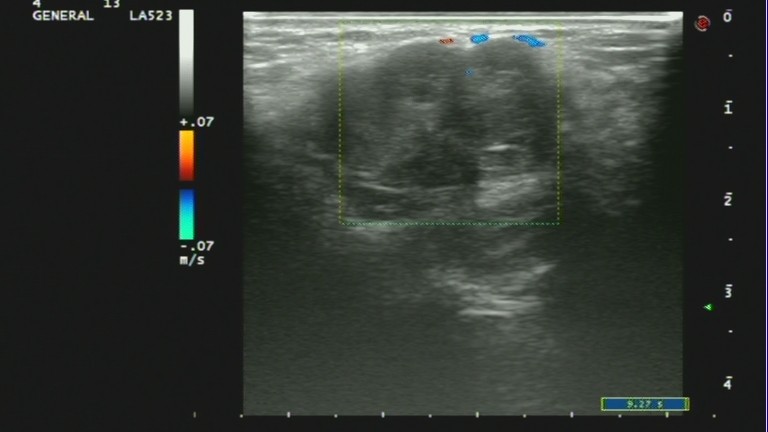

1、肿块多呈不均质的低回声,没有包膜,后方回声可衰减。

2、肿块不规则,会有分叶情况,典型的有“蟹足状”。

3、边界不清,毛刺状边缘。

4、高大于宽,即是纵横比大于1。

5、有微小钙化。

6、肿块内血流丰富,不规则,多为高频、高阻血流。